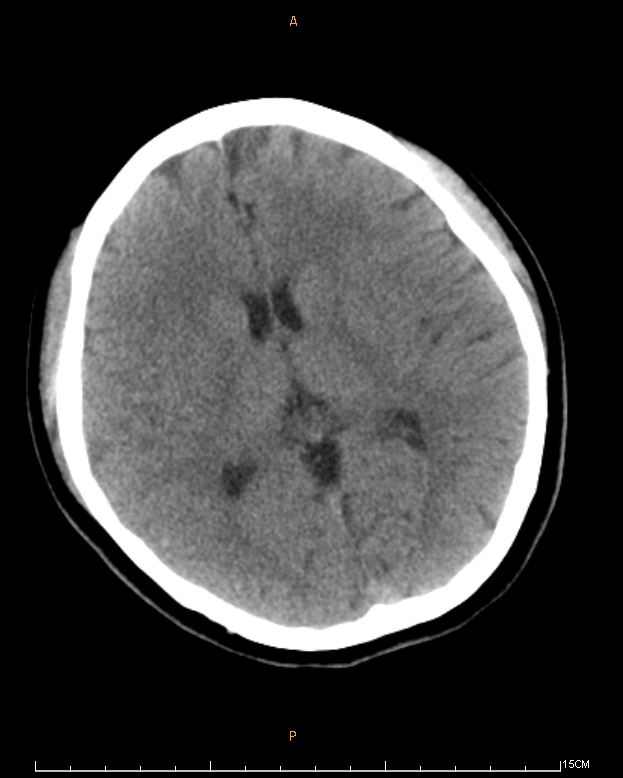

A 24-year-old womanexperienced nausea and abdominal discomfort days before a shortsyncope episode. She was taken to a local hospital. EKG showed sinustachycardia, low QRS voltage, and ST elevation over aVR, V1-3. CT scan of the brain revealed no signs of intracranial hemorrhage. Shewas transferred to our hospital under norepinephrine infusion.

At triage, she wasalert but hypotensive. Labs showed elevated troponin-T and NT-pro BNPlevels and leukocytosis. CXR showed perihilarinfiltrates, and TTE indicated mild LVEF reduction and globalhypokinesia of LV. Given the suspicion of fulminant myocarditis, shebegan IVIG therapy.